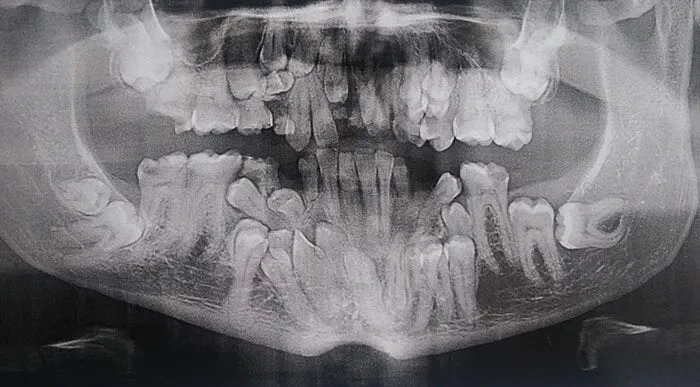

준비된사람되기님의 댓글 준비된사람되기이름으로 검색이름으로 검색 작성일 12.07 23:41 유치 밑에 영구치도 보이고.. 아직 어린애 같은데 어금니 보니 암담하네요.. 신고 추천0비추천0 유치 밑에 영구치도 보이고.. 아직 어린애 같은데 어금니 보니 암담하네요..